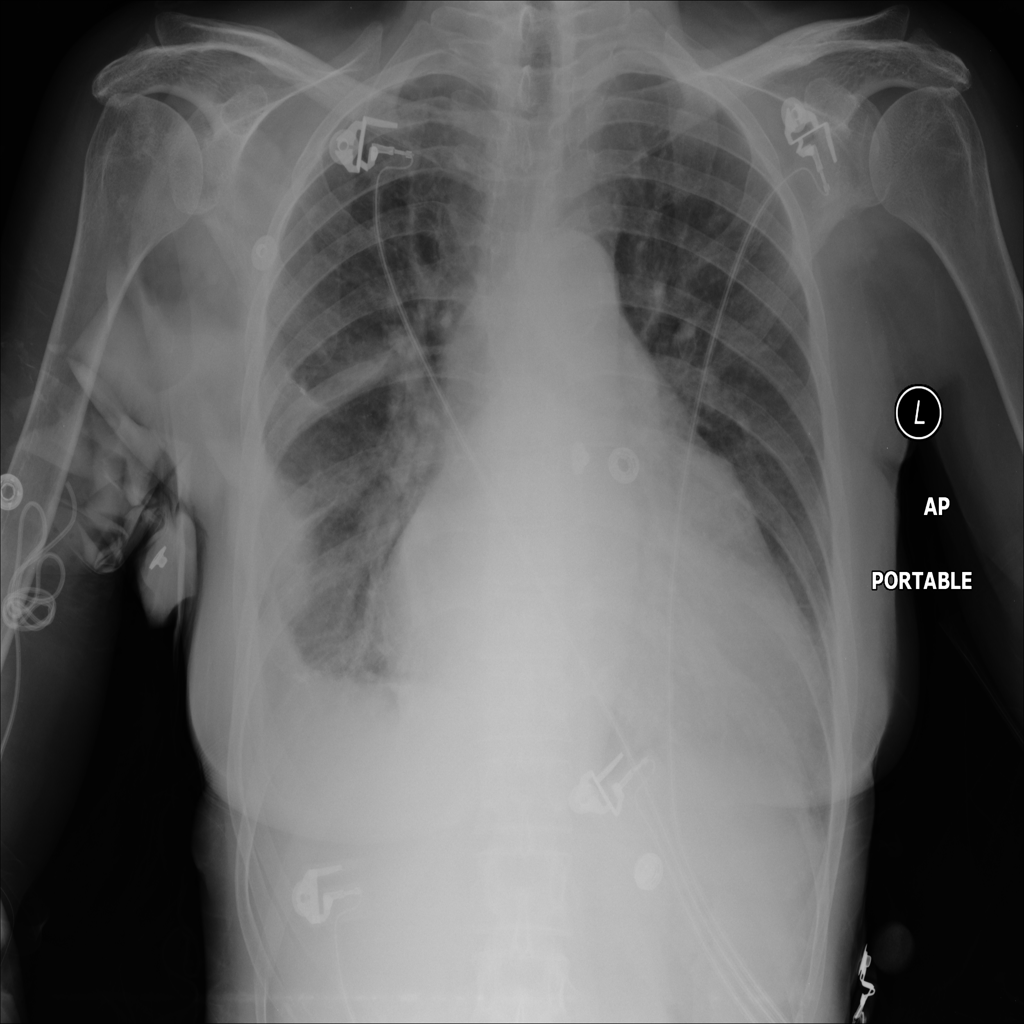

PAT-C0E5 · IMG-002Effusion

PAT-C0E5 · IMG-002

PA